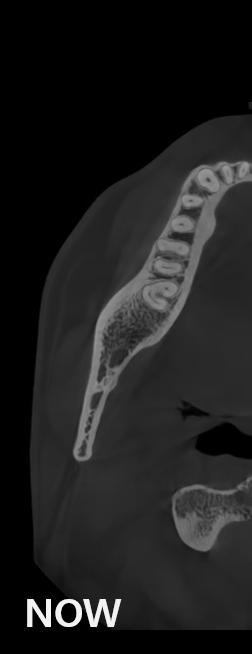

¡Evolución continua, más clara, más precisa!

La tecnología de imágenes de HDXWILL se actualiza constantemente a través de la investigación continua.

Los algoritmos matemáticos que reflejan las propiedades físicas y el avanzado motor de IA aprendido a partir de varios datos trabajan juntos para reducir el ruido y hacer que las estructuras dentales sean más claras.